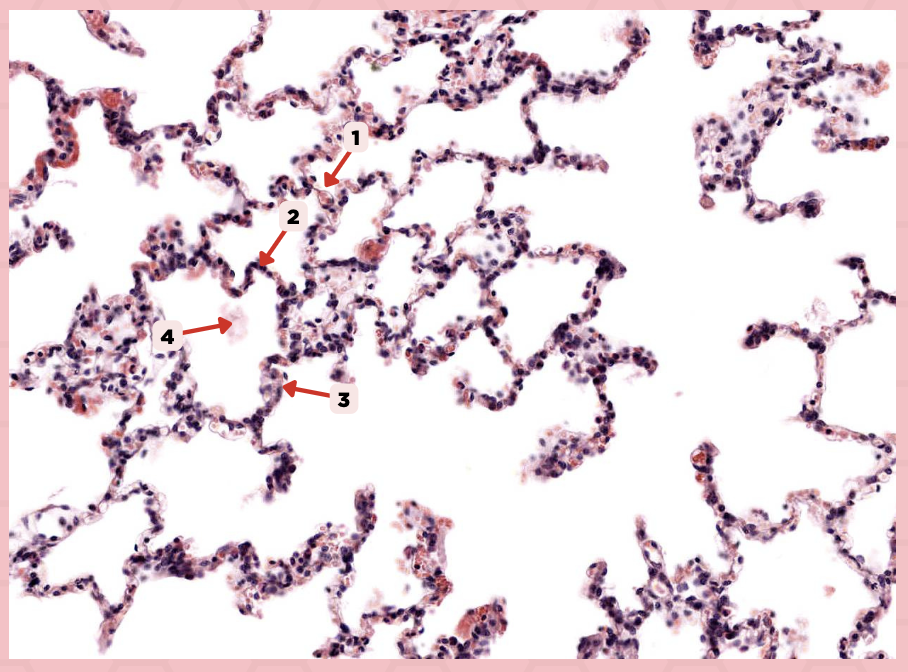

Interalveolar septum

Identify the structure labeled as 1.

Type I alveolar cell

Identify the structure labeled as 2.

Type II alveolar cell

Identify the structure labeled as 3.

Pulmonary Alveolar Macrophages (Dust Cells)

Identify the structure labeled as 4.

Pulmonary Alveolar Macrophages (Dust Cells)

What are the most numerous cells inside the alveoli?

Pneumocyte Type I

Which of the following labeled structures covers 95% of the alveolar surface?

Type I alveolar cell

Identify the structure labeled as 1.

Type II alveolar cell

Identify the structure labeled as 2.

Pulmonary Alveolar Macrophages (Dust Cells)

Identify the structure labeled as 3.

Endothelial Cells

Identify the structure labeled as 4.